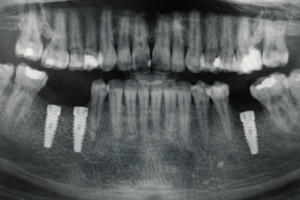

Implantes Dentales Convencionales

Tratamiento destinado a reemplazar dientes perdidos mediante la colocación de implantes de titanio en el hueso maxilar o mandibular. Permite recuperar la función masticatoria, la estética dental y la estabilidad de la mordida de forma segura y duradera.